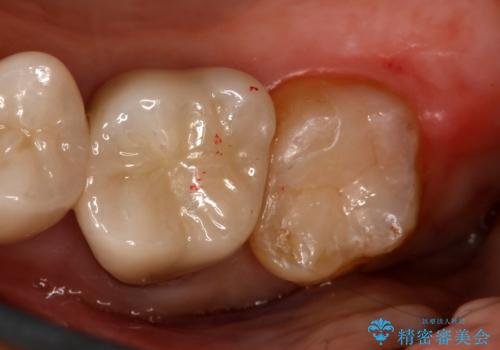

- 右上7番の銀歯のやりかえを主訴に来院された患者様です。

切削量・形態を考慮し、セラミックインレーでの治療を計画しました。

インレー治療では自分の歯を多く残すことが出来ます。